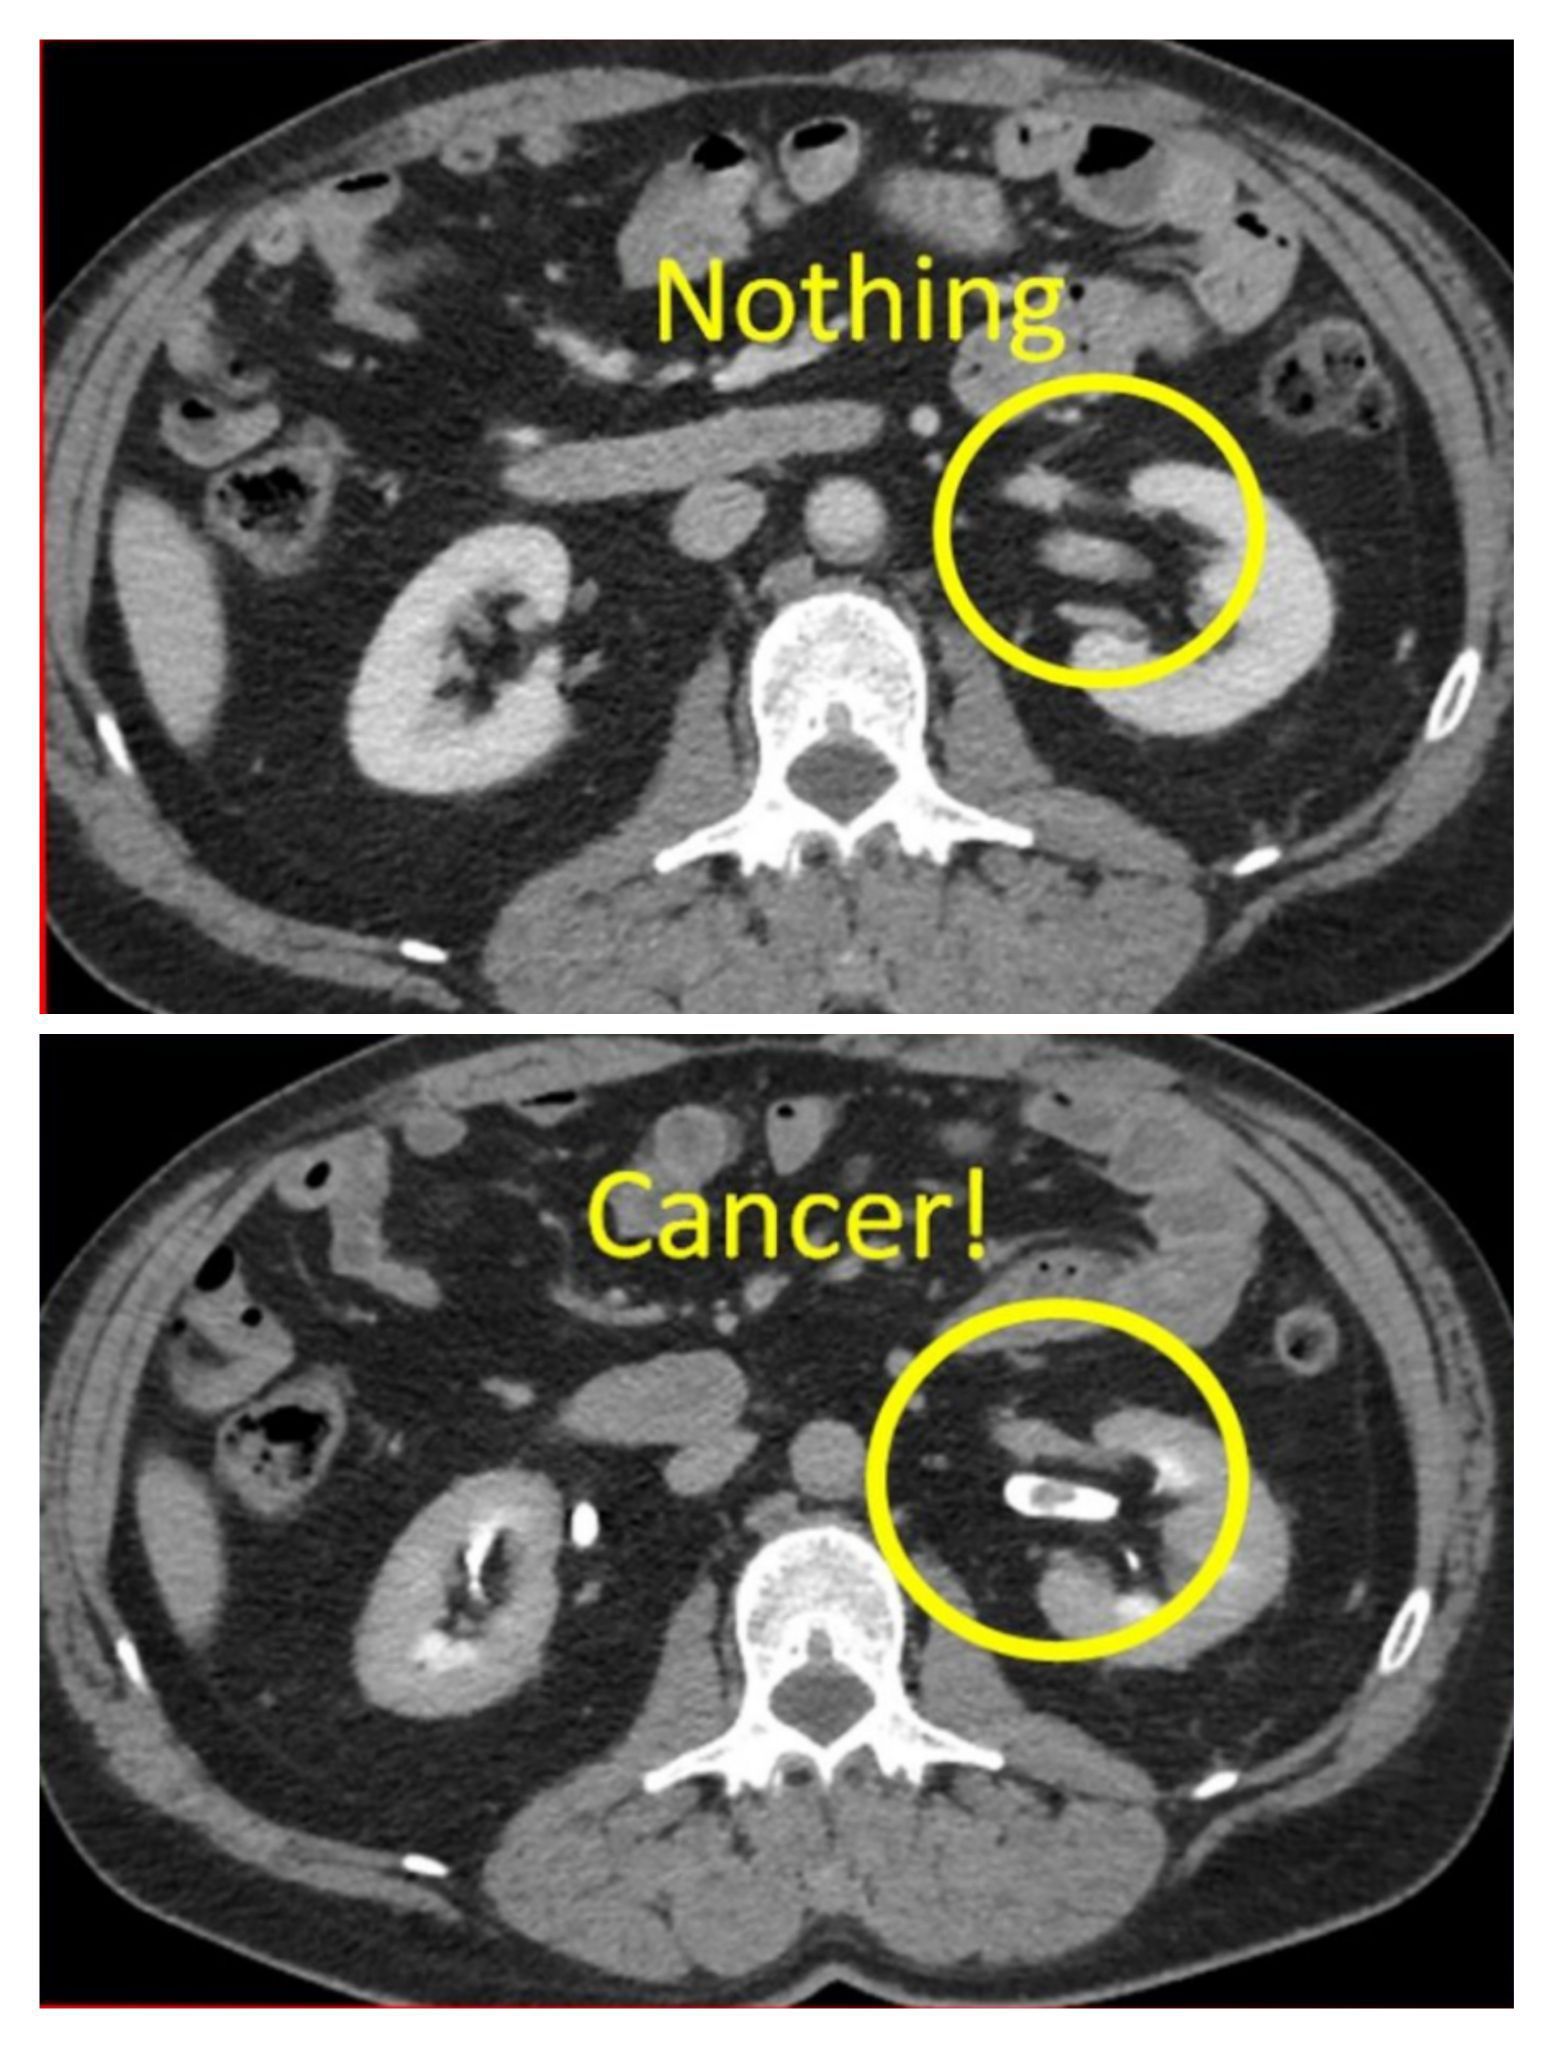

Transitional cell carcinoma- Nephrographic phase CT shows no abnormality in the left kidney collecting system. . . Pyelographic phase CT shows an oval soft tissue mass in the collecting representing a transitional cell carcinoma. . . If we only had the standard nephrographic phase image we would have missed this cancer! That’s why it is so important to do a CT urogram whenever there is hematuria. . . Transitional cell carcinoma is the most common primary malignancy of the urinary tract and may be found along its entire length (renal pelvis to the bladder). The most common presentation is hematuria. The vast majority are seen in the bladder (97%). .